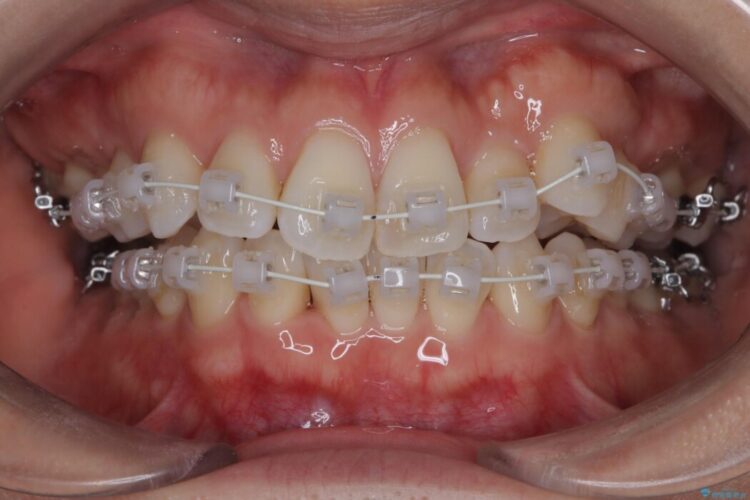

全体的にスペース不足ではありましたが、患者様は抜歯をしたくないとのご要望だったため、上顎の裏側に「トランスパラタルアーチ(TPA)」という装置を装着し、奥歯の幅を調整しながらスペースを確保する計画を立案。

矯正装置は目立ちにくい審美ワイヤーを使用しています。